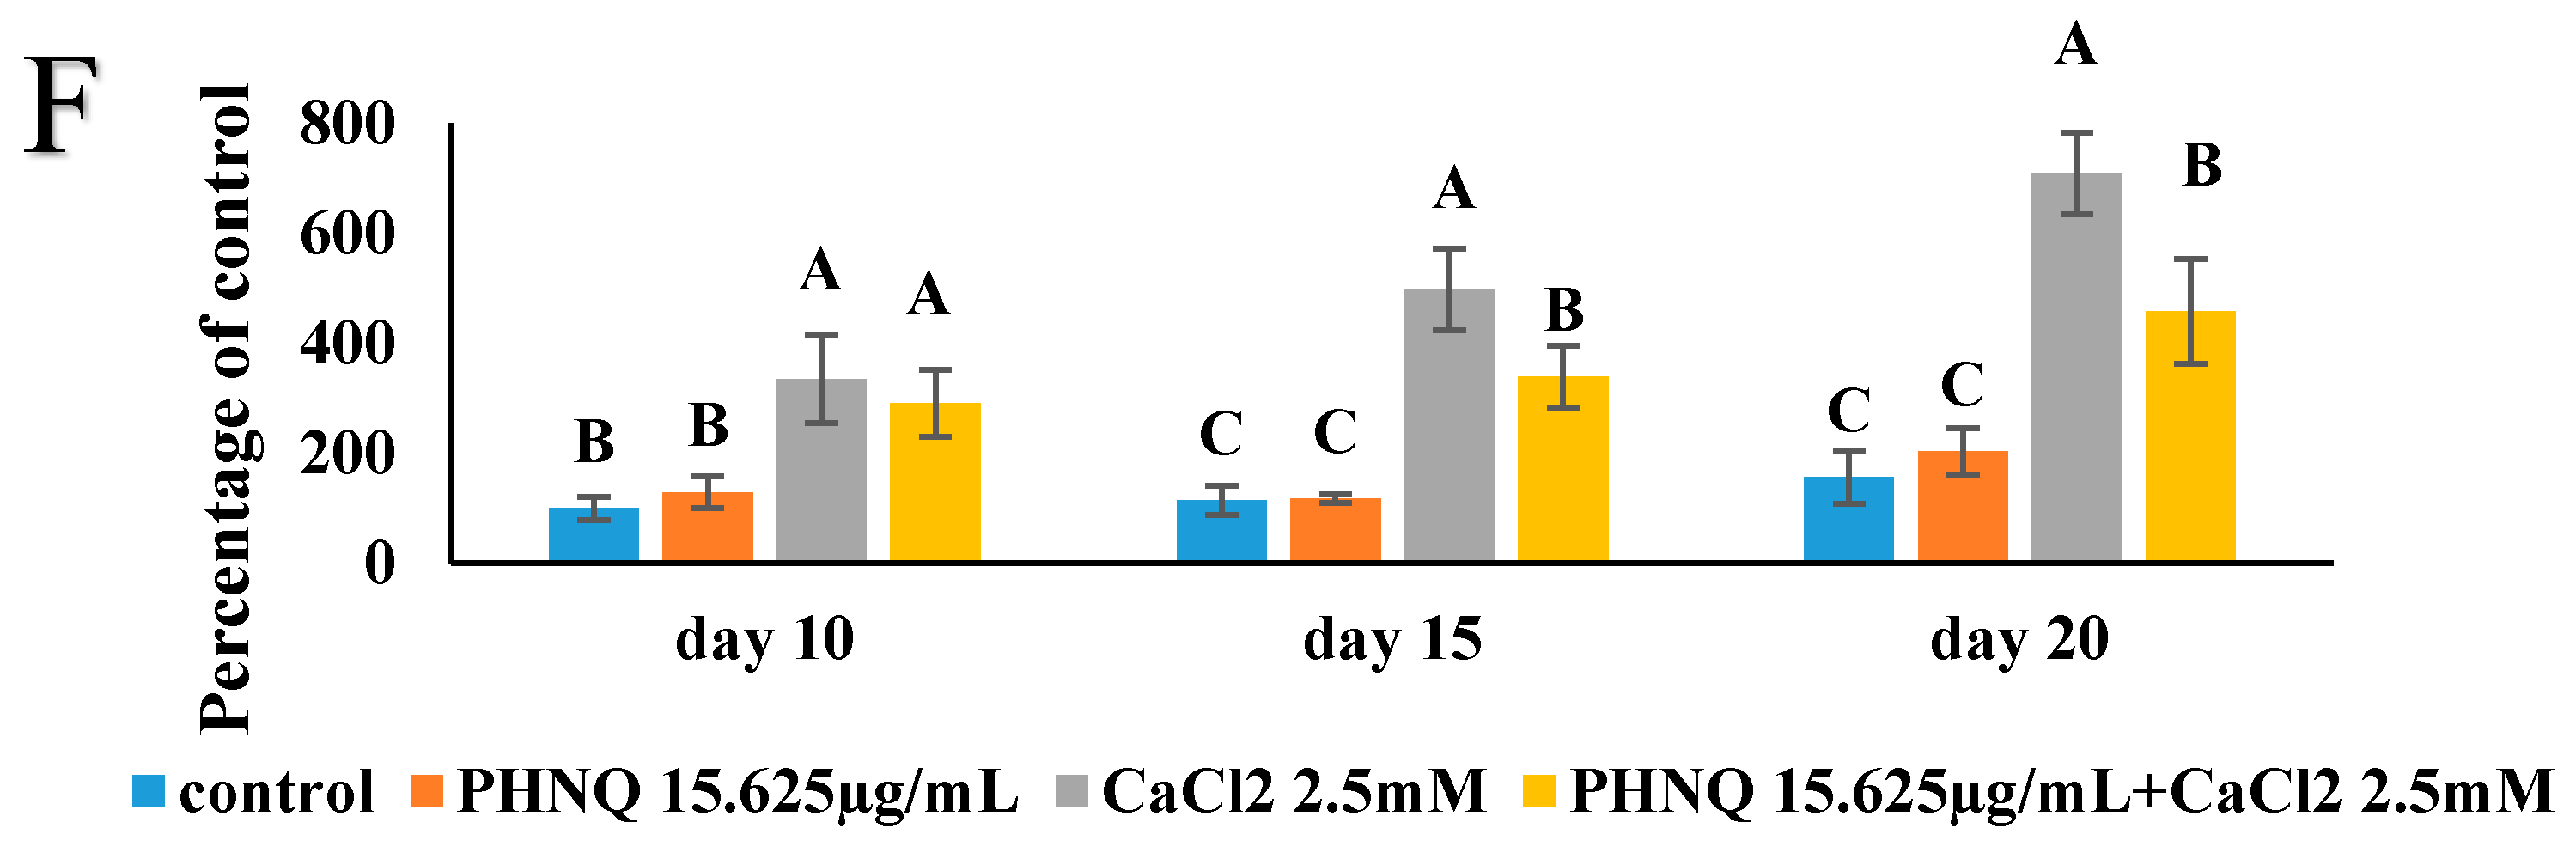

2.7. Effect of PHNQ on Mineralization in the Presence of CaCl2